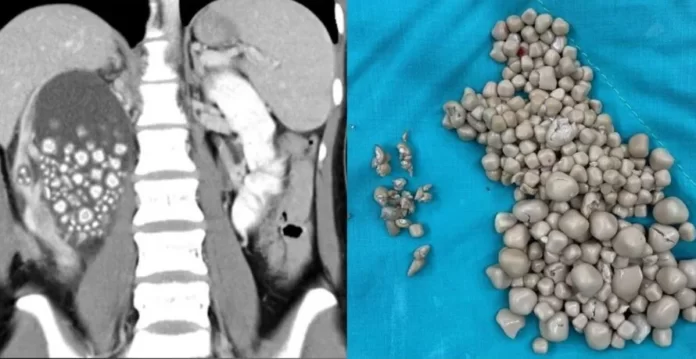

Uma jovem de 20 anos precisou passar por uma cirurgia de emergência para retirar mais de 300 pedras de um dos seus rins. O caso ocorreu no Hospital de Chi Mei, em Taiwan.

A mulher compareceu na instituição de saúde apresentando sintomas como febre e dores no quadril. Exames de imagem revelaram a presença de um grande número de pedras no rim esquerdo dela.

As maiores pedras entre as centenas retiradas do corpo da jovem tinham cerca de 2 centímetros de diâmetro.

Foi feita uma nefrolitotripsia percutânea, procedimento considerado minimamente invasivo, em que as pedras são retiradas por um pequeno corte feito nas costas.